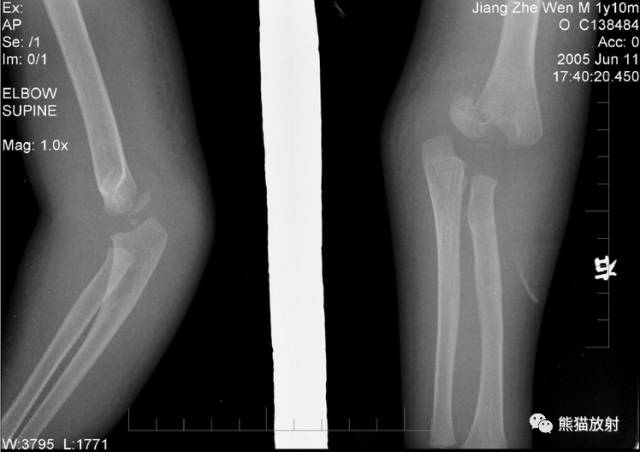

肱骨远端全骺分离

1岁男孩,肘关节外伤一天